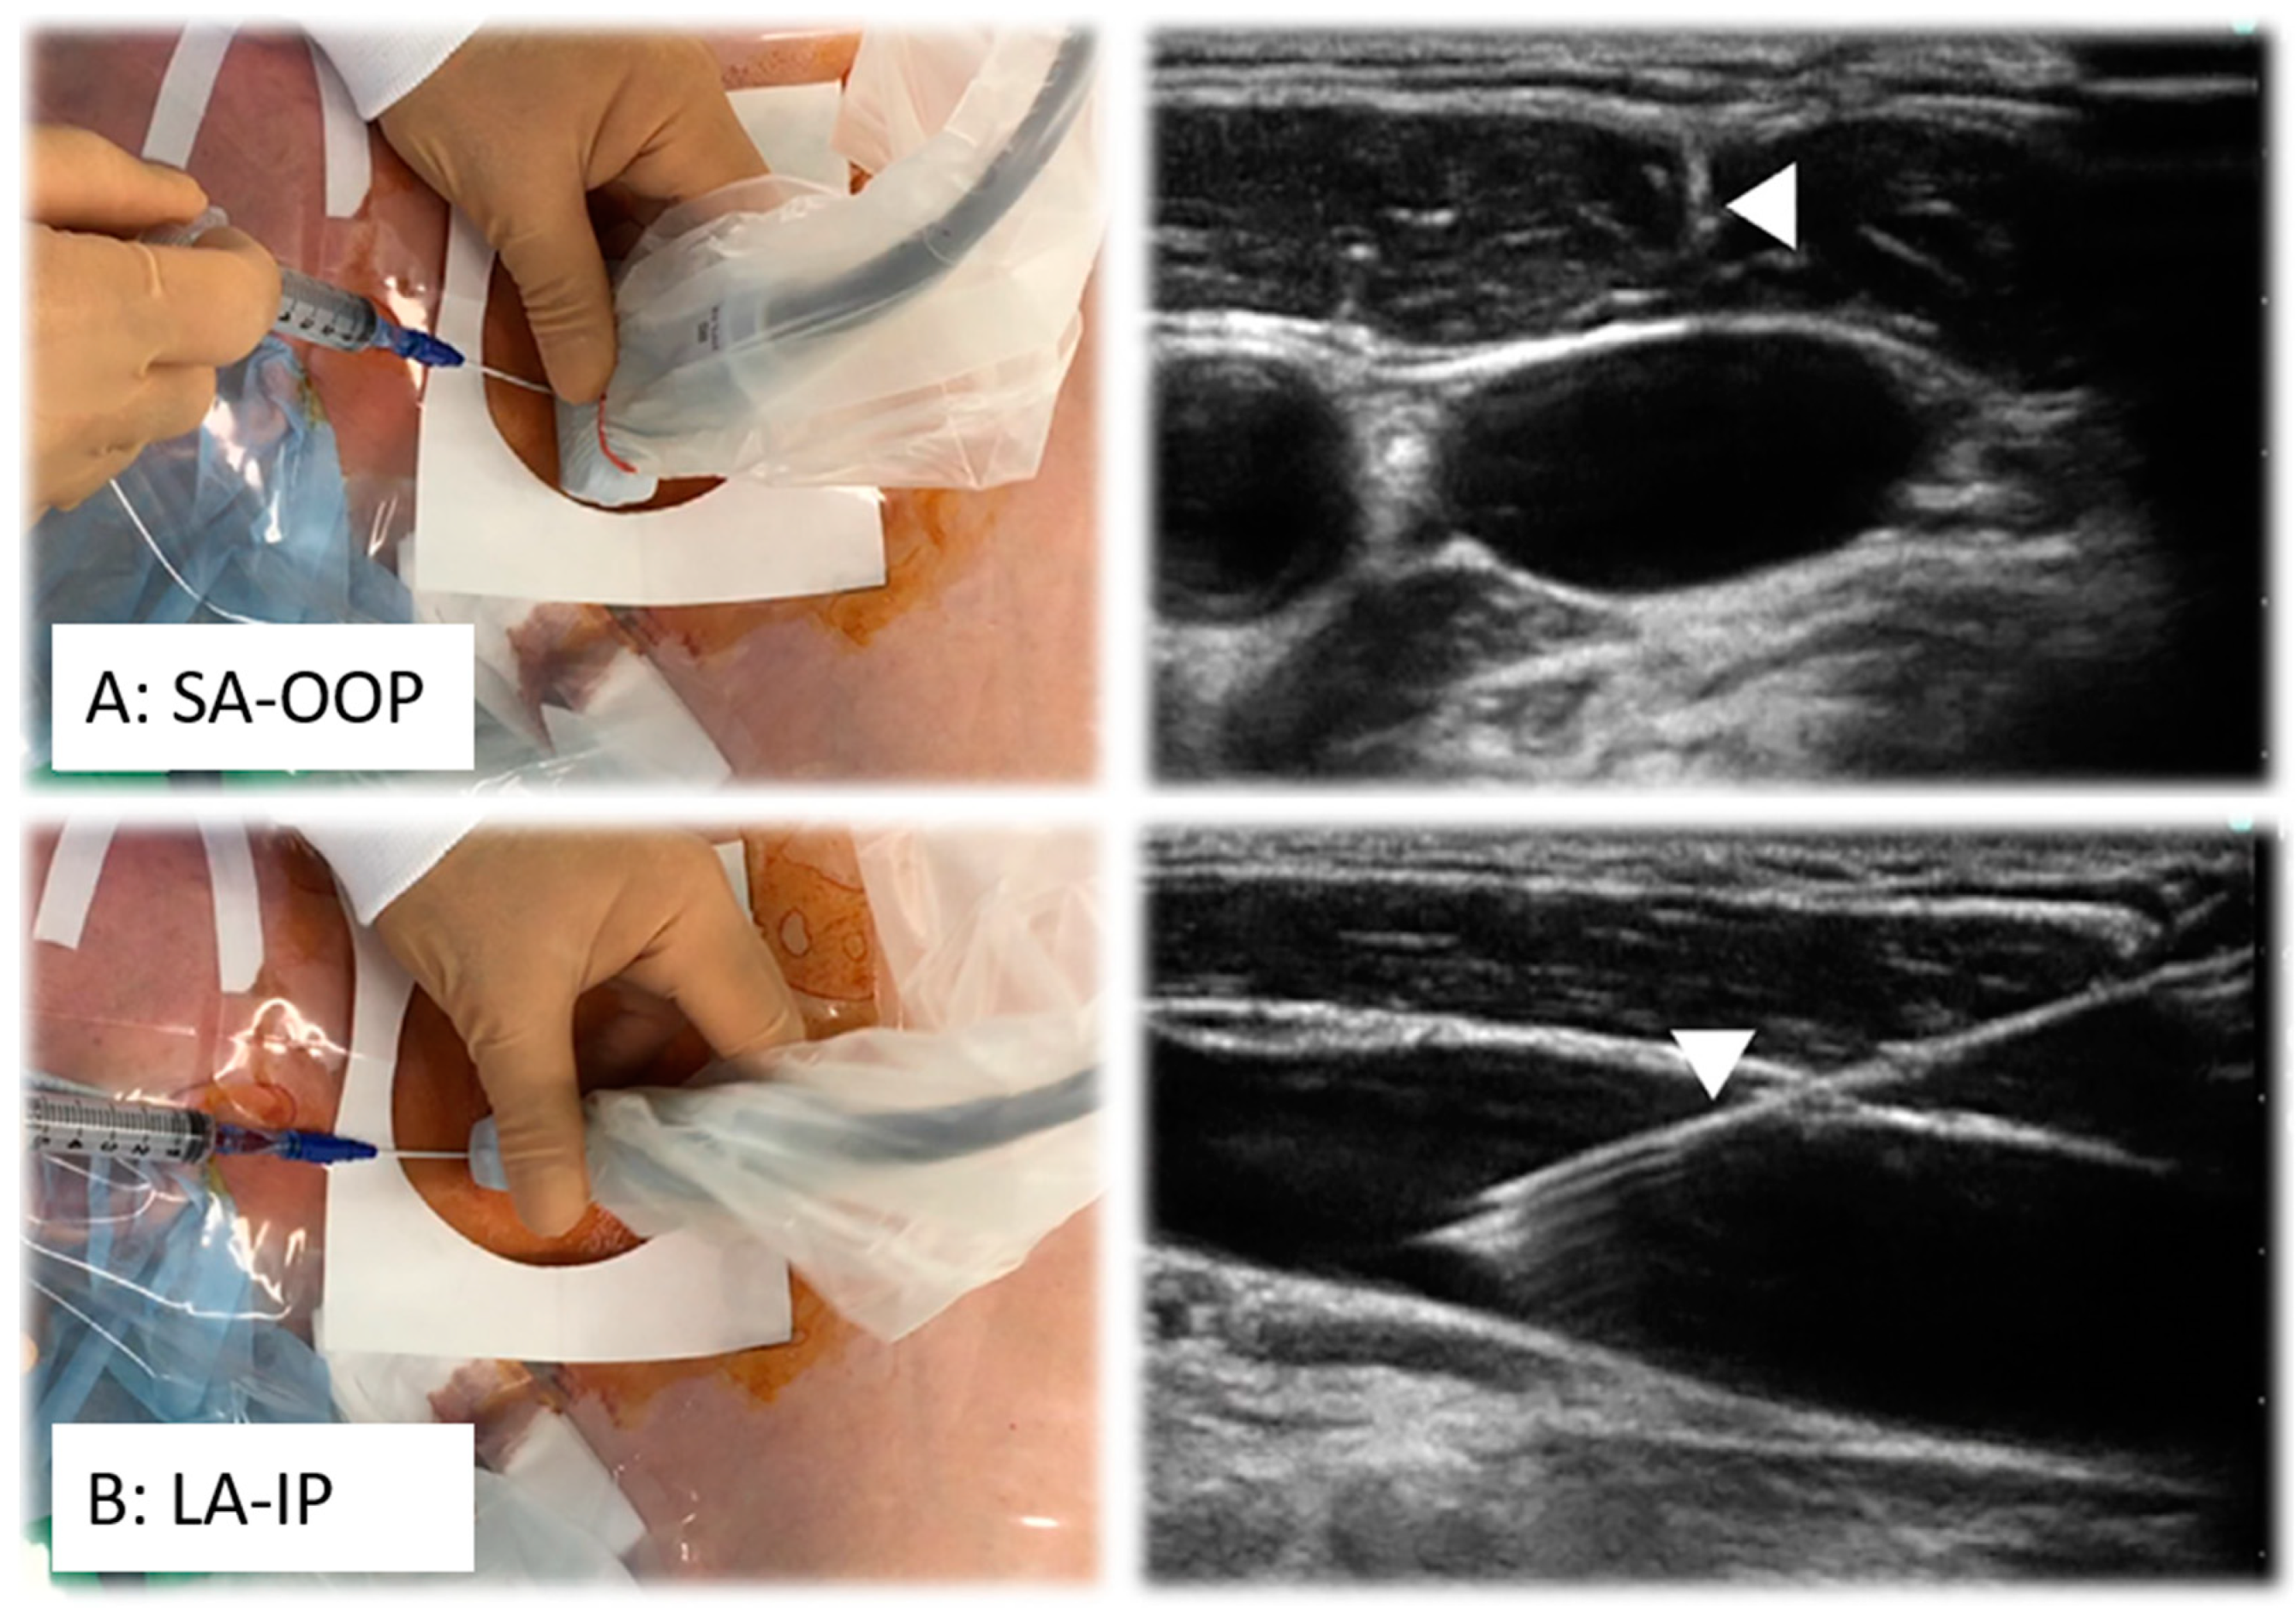

- Sung, J.M.; Jun, Y.E.; Jung, Y.D.; Kim, K.N. Comparison of an Ultrasound-Guided Dynamic Needle Tip Positioning Technique and a Long-Axis In-Plane Technique for Radial Artery Cannulation in Older Patients: A Prospective, Randomized, Controlled Study. J. Cardiothorac. Vasc. Anesth. 2023, 37, 2475–2481. [Google Scholar] [CrossRef] [PubMed]

- Takeshita, J.; Nishiyama, K.; Fukumoto, A.; Shime, N. Comparing Combined Short-Axis and Long-Axis Ultrasound-Guided Central Venous Catheterization With Conventional Short-Axis Out-of-Plane Approaches. J. Cardiothorac. Vasc. Anesth. 2019, 33, 1029–1034. [Google Scholar] [CrossRef] [PubMed]